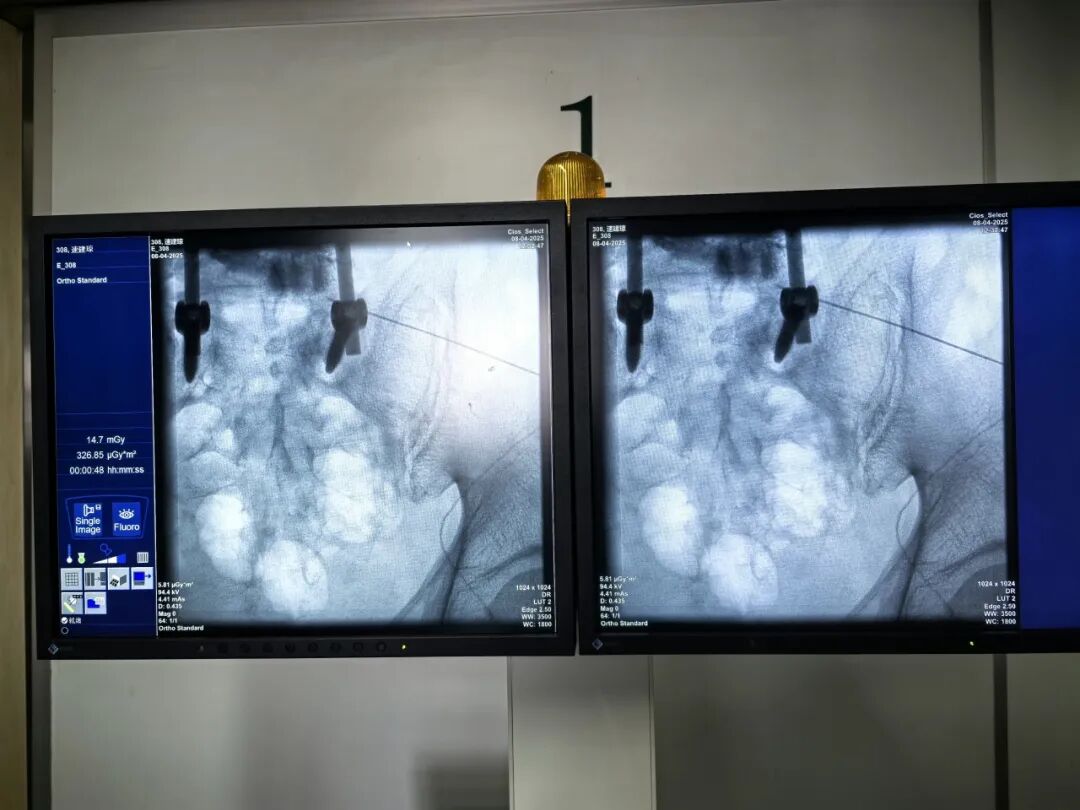

朱先生腰椎手术后仍持续腰痛,日常活动受限。经团队详细评估,确诊为脊神经后支卡压导致的复杂性疼痛。团队采用“C臂引导下脊神经后支射频消融术”,通过热凝技术精准灭活病变神经分支。术后患者腰痛即刻缓解90%,次日即可自主下床活动。该技术仅需局部麻醉,全程30分钟,真正实现"当天治疗、当天回家"的微创理念。